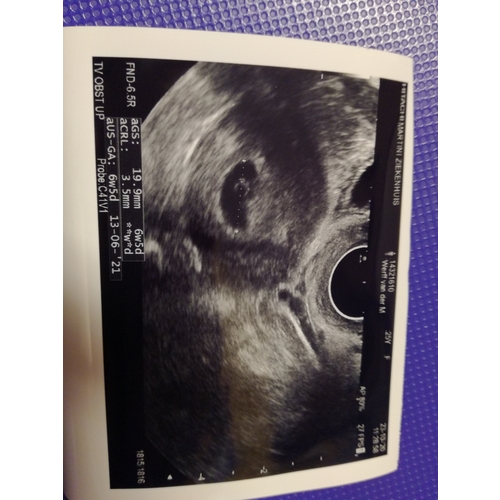

Mijn 5 a 6 mm gister met 6+6 eigen schatting

Bij 6+5 weken 9,36mm, ze zei wel dat ze het niet heel precies kon meten dus kan ook iets minder of meer zijn geweest.